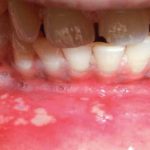

Each of us at least once in my life heard such a term as stomatitis (picture 1), but not everyone knows about its main types and forms (such as, angular, aphthous, herpetic, gingivostomatitis) that we consider further.

Inflammation of the oral mucosa is called stomatitis (picture 1). What is it and why does this disease occur? The cause of the pathological process can be a variety of infectious agents, and it can provoke a decrease in the immune system, poor nutrition, stress, injuries to the oral cavity.

Aphthous stomatitis (picture 3) is accompanied by the appearance in the mouth of the so-called aft or erosion. This process is very unpleasant, patients experience a characteristic burning sensation. The disease can also complicate meal.

May experience hyperthermia and local lymphoedema. Not treated thrush can become chronic. Read more in the article about aphthous stomatitis on our website.